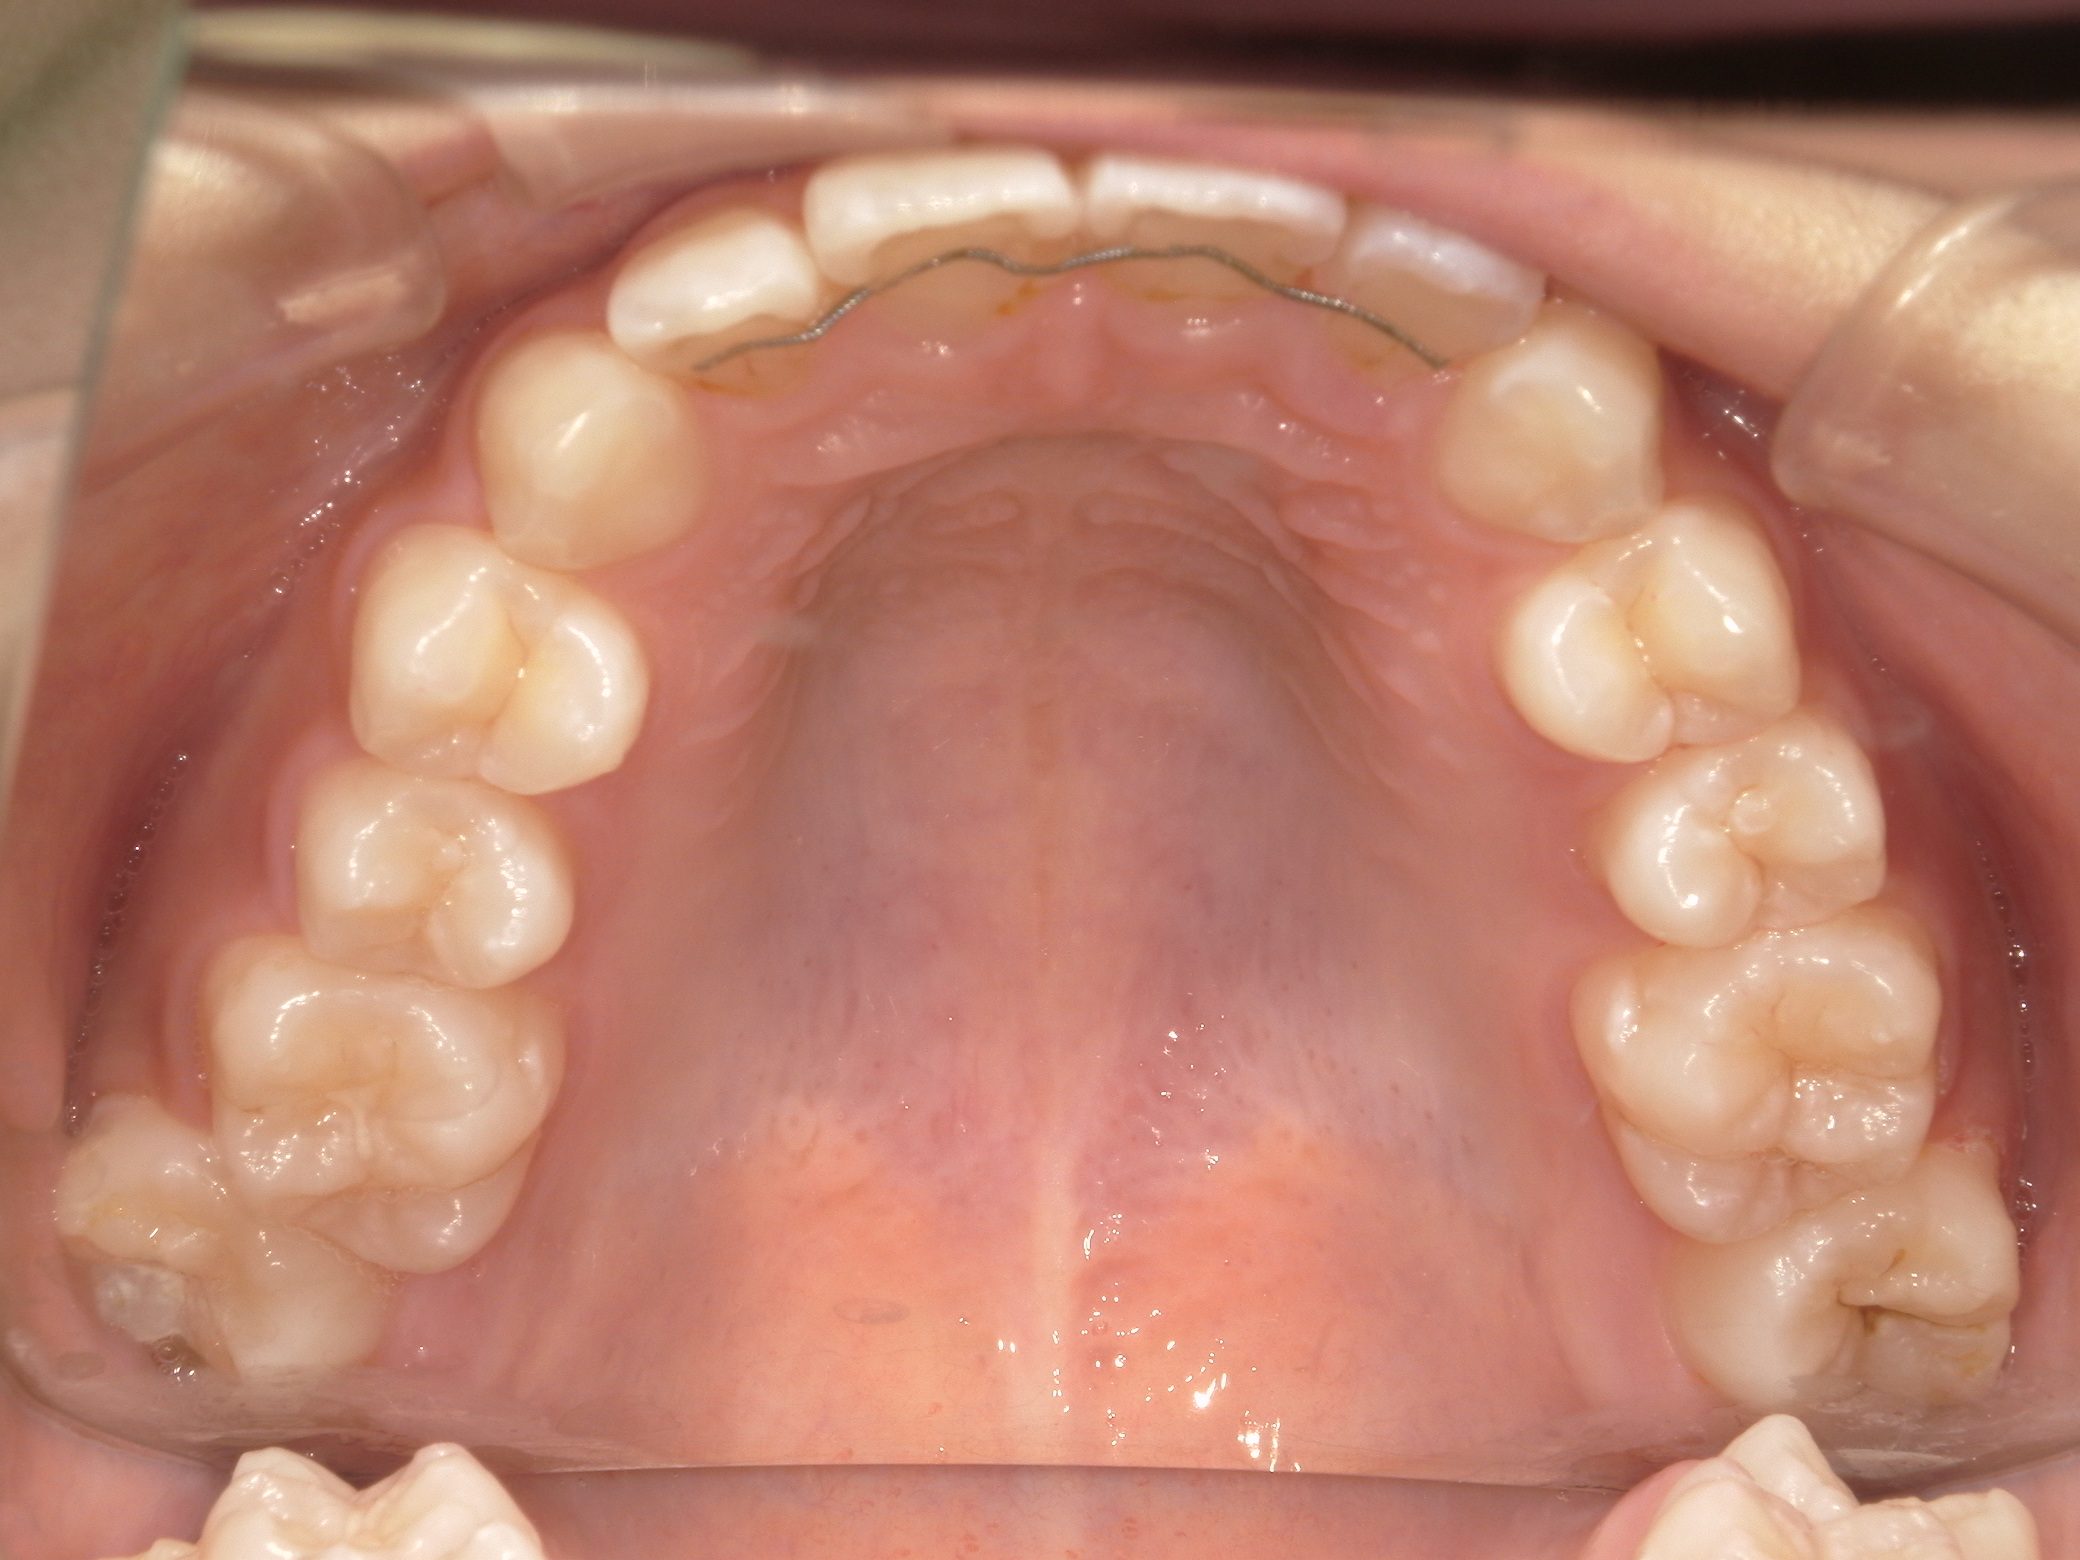

Before

After

舌癖が原因で、前歯が動揺していましたが、矯正治療を開始して動揺は収まりました。

矯正後、写真撮影時は 外傷で歯を打って動揺が出た時期だったため、 後ろから固定しています。

afterの写真は全て永久歯列になった時の写真です。